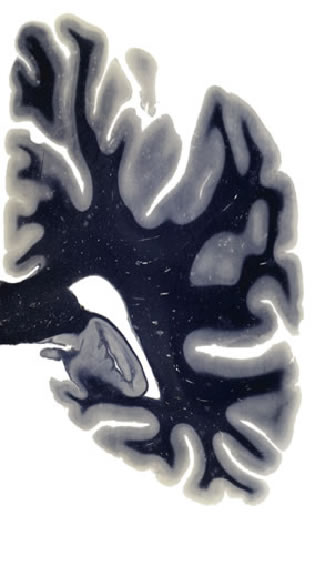

Hi-Resolution Sections · Cells (Nissl Staining) · Virtual Microscopy

Frontal sections (Nissl) from the Atlas Brain:

Slice ID:

r4-0220

Plate NR:

52

Position:

42,7 mm